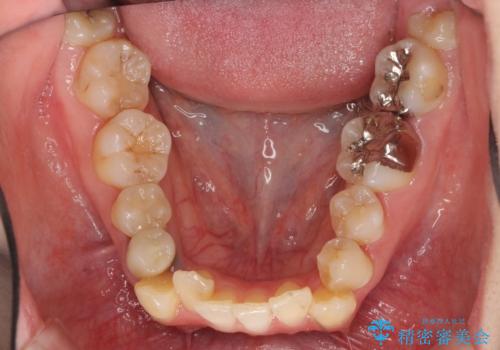

前歯のがたつきを主訴に来院。

ワイヤー矯正の古典的な治療方針である、4本抜歯して全体ワイヤーでも構わないとのことでした。

4本抜歯すると口元が下がりすぎてしまうため、下の前歯のみ1本抜歯および上顎の前歯が大きいため少し削らせてもらう提案をしました。

右上2番をしっかり並べるにはワイヤー矯正を上顎部分的に用いて、最後全体マウスピース治療を行いました。